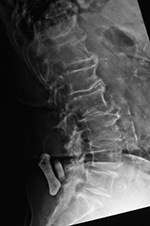

| 59 year-old man with past history of C3-5 fractures and extensive posterior spinal fixation from the occiput to T8. Lateral radiographs of the cervical spine three months apart show dislodgement (arrow) of the bilateral cervical posterior rods from connection with the thoracic rods at the C7-T1 level. Left: before dislodgement. Right: after dislodgement. After dislodgement there is increased kyphosis at the C6-7 level. |

From Hunter, 2004 |